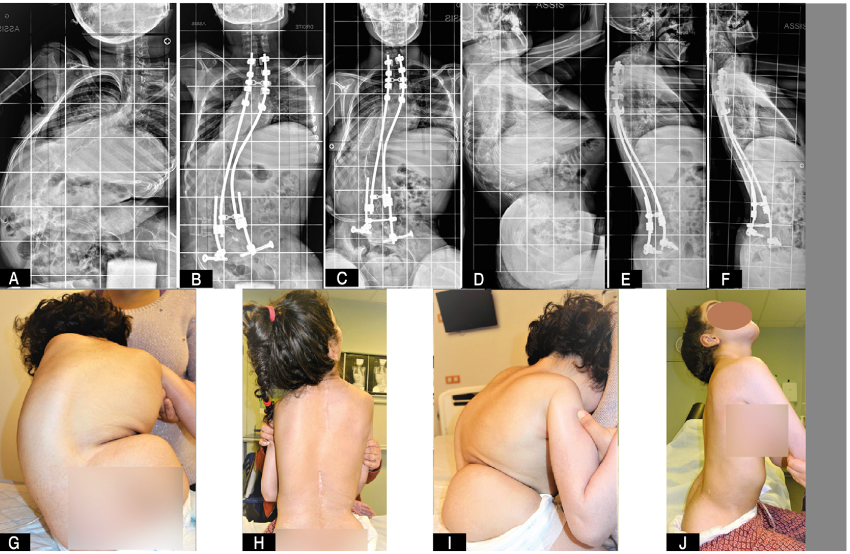

Escoliose neuromuscular (paralisia cerebral, distrofias, amiotrofias, entre outras)

A escoliose neuromuscular ocorre como consequência de um desequilíbrio muscular associado a doenças neurológicas ou musculares, como paralisia cerebral, distrofias musculares e amiotrofias. Diferentemente da escoliose idiopática, esse tipo de escoliose costuma apresentar progressão mais rápida e curvas mais extensas.

Com frequência, está associada a outros problemas, como:

- inclinação da pelve (obliquidade pélvica);

- dificuldade para manter a postura sentada;

- comprometimento respiratório;

- dor e prejuízo funcional progressivo.

Tratamento conservador na escoliose neuromuscular

O tratamento conservador, incluindo o uso de coletes, tem papel limitado no controle definitivo da deformidade. Em muitos casos, o objetivo principal não é impedir a progressão da curva a longo prazo, mas sim:

- oferecer suporte postural;

- melhorar o conforto;

- facilitar cuidados diários, como higiene e posicionamento.

Desse modo, a literatura descreve que, em curvas progressivas, o tratamento conservador raramente consegue evitar a evolução da deformidade de forma duradoura.

Tratamento cirúrgico na escoliose neuromuscular

O pilar do tratamento para escolioses neuromusculares progressivas, tem sido o tratamento cirúrgico, especialmente quando há comprometimento da função, dificuldade para sentar, dor, obliquidade pélvica significativa ou impacto respiratório.

Em geral, o procedimento envolve uma artrodese longa da coluna, realizada pela via posterior, com hastes e parafusos, com atenção especial ao alinhamento global da coluna e da pelve.

Estudos e revisões sistemáticas mostraram que a cirurgia pode trazer melhora na qualidade de vida, no posicionamento sentado e no conforto do paciente. No entanto, trata-se de um procedimento complexo, associado a taxas mais elevadas de complicações, o que exige avaliação criteriosa e planejamento individualizado.

Tendência atual: técnicas menos invasivas e correção progressiva

Diante das altas taxas de complicações associadas às artrodeses extensas, especialmente em pacientes frágeis, houve nos últimos anos uma tendência ao desenvolvimento e à utilização de técnicas menos invasivas, aplicadas de forma mais precoce.

Uma dessas abordagens é a técnica bipolar descrita pelo professor Lofti Miladi, amplamente divulgada na literatura especializada. Essa técnica utiliza pontos de fixação proximais e distais, permitindo uma correção progressiva da deformidade, acompanhando o crescimento e a adaptação do corpo, com:

- menor agressão cirúrgica inicial;

- menor impacto sobre o crescimento;

- possibilidade de adiar cirurgias maiores.

Essa estratégia busca equilibrar controle da deformidade, preservação funcional e redução de riscos em pacientes com escoliose neuromuscular.